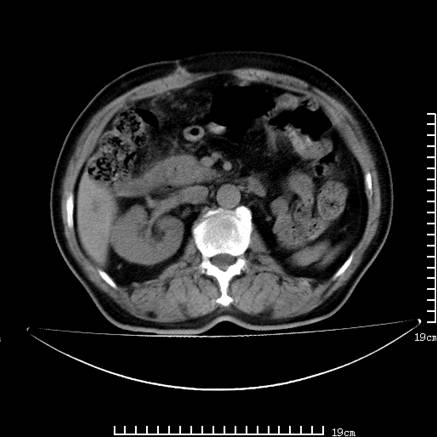

以下是引用lirenxiong在2008-7-19 22:01:00的发言:[br]胆总管结石并胆系感染,胆囊切除术后改变!左肾未见!左肾上腺增生肥大?请全腹扫描,增强!

以下是引用zsl6918在2008-7-19 21:53:00的发言:[br]胆总管结石并胆系感染,胆囊切除术后改变。